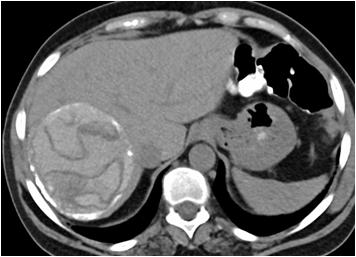

Ultrasound studies : Ultrasound showed cystic lesions in 17 patients and solid masses in three. Medial locations of a cystic retro-vesical mass were consistent with a prostatic utricle cyst (Fig 1) or abscess (Fig 2). Transrectal ultrasound was performed

additionally in eight patients to confirm the intraprostatic or extra-prostatic location of the cysts. Ultrasound revealed mixed echogenic masses in all the three patients with retro-vesical teratoma (Fig 3) which was difficult to differentiate from haematoma and four patients had cystic lesion contained hyperechoic material consistent with dermoid cyst but one letter on confirm on HPE was mullerian duct cyst with cystadenoma. A cystic extra-prostatic mass lateral to

the bladder neck was demonstrated on ultrasound for all seminal vesicle (Fig 4).